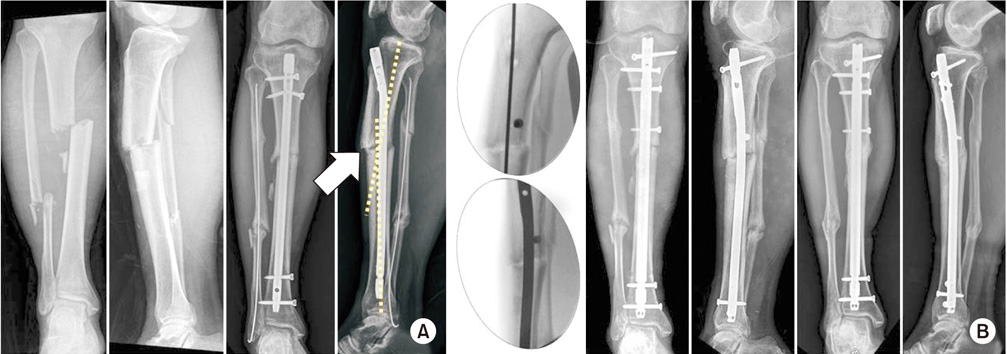

(A) After intramedullary nailing of the proximal tibial shaft fracture, non-union with anterior angulation was confirmed. The center of rotation of angulation was identified (arrow). (B) The angulation was corrected by exchanging the nailing with a blocking screw at the proximal fragment. Six months later, the bony alignment and union was achieved.

Fig. 3 (A) After intramedullary nailing of the proximal tibial shaft fracture, non-union with anterior angulation was confirmed. The center of rotation of angulation was identified (arrow). (B) The angulation was corrected by exchanging the nailing with a blocking screw at the proximal fragment. Six months later, the bony alignment and union was achieved.